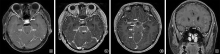

目的: 探讨磁共振三维颅脑容积成像(three-dimension brain volume imaging,3D BRAVO)增强扫描在颅内结核影像诊断中的价值。方法: 收集2021年4月至2024年8月首都医科大学附属北京胸科医院临床确诊及资料完整的122例颅内结核患者作为研究对象。所有患者均进行了结核病相关实验室检查(包括脑脊液检测)、头颅磁共振平扫及增强扫描检查,以及磁共振3D BRAVO增强扫描检查。分析研究对象头颅磁共振常规增强扫描及3D BRAVO增强扫描的影像学特点,并评价磁共振3D BRAVO增强扫描在颅内结核影像诊断中的价值。结果: 患者临床表现存在结核中毒症状和呼吸系统症状(如咳嗽、咳痰、胸痛等)者32例(26.2%,32/122);出现发热、头痛者81例(66.4%,81/122);具有神经系统症状和体征者73例(59.8%,73/122),其中,脑脊液实验室检查常规和生化异常者113例(92.6%,113/122)。所有患者均行腰椎穿刺术检查,颅内压高于180mmH2O(1mmH2O=0.0098kPa)者57例(46.7%,57/122)。122例患者头颅常规磁共振增强扫描:30例(24.6%,30/122)显示为脑膜型,40例(32.8%,40/122)显示为脑实质型,29例(23.8%,29/122)显示为混合型(脑膜及脑实质病变并存),23例(18.9%,23/122)未见颅内结核病变;磁共振3D BRAVO增强扫描:43例(35.2%,43/122)显示为脑膜型,22例(18.0%,22/122)显示为脑实质型,45例(36.9%,45/122)为混合型,12例(9.8%,12/122)未见颅内结核病变。磁共振3D BRAVO增强扫描对颅内结核患者病灶检出率明显高于头颅磁共振常规增强扫描,差异有统计学意义(χ2=9.091,P=0.001);对脑膜结核的检出率明显高于头颅磁共振常规增强扫描,差异有统计学意义(χ2=27.034,P<0.001)。磁共振3D BRAVO增强扫描122例患者中,9例并发脑积水、29例并发脑梗死、10例并发脑神经病变。结论: 磁共振3D BRAVO增强扫描对颅内结核的分型和早期发现具有重要辅助诊断价值。

Objective: To investigate the value of three-dimensional brain volume imaging (3D BRAVO) contrast-enhanced magnetic resonance imaging (MRI) in the imaging diagnosis of intracranial tuberculosis. Methods: A total of 122 patients with intracranial tuberculosis who were clinically diagnosed and had complete data at Beijing Chest Hospital affiliated to Capital Medical University from April 2021 to August 2024 were collected as the research subjects. All patients underwent tuberculosis related laboratory tests (including cerebrospinal fluid testing), cranial MRI plain and enhanced scans, and 3D BRAVO enhanced MRI scans. The imaging characteristics of the study subjects’ skull magnetic resonance conventional enhanced scan and 3D BRAVO enhanced scan were analyzed, and the value of magnetic resonance 3D BRAVO enhanced scan in the imaging diagnosis of intracranial tuberculosis was evaluated. Results: Thirty-two cases (26.2%, 32/122) had clinical manifestations of tuberculosis poisoning and respiratory symptoms (such as cough, sputum, chest pain, etc.); 81 cases (66.4%, 81/122) experienced fever and headache; 73 cases (59.8%, 73/122) had neurological symptoms and signs, among which 113 cases (92.6%, 113/122) had routine and biochemical abnormalities in cerebrospinal fluid laboratory tests. All patients underwent lumbar puncture examination, and 57 cases (46.7%, 57/122) had intracranial pressure higher than 180 mmH2O (1 mmH2O=0.0098 kPa). All patients underwent routine magnetic resonance enhanced scans of their heads: 30 cases (24.6%, 30/122) showed meningeal type; 40 cases (32.8%, 40/122) showed parenchymal type, 29 cases (23.8%, 29/122) showed mixed type (meningeal and parenchymal lesions coexisted), 23 cases (18.9%, 23/122) showed no intracranial tuberculosis; Magnetic resonance 3D BRAVO enhanced scan: 43 cases (35.2%, 43/122) showed meningeal type; 22 cases (18.0%, 22/122) showed cerebral parenchyma type, 45 cases (36.9%, 45/122) showed mixed type, and 12 cases (9.8%, 12/122) showed no intracranial tuberculosis. The detection rate of lesions in intracranial tuberculosis patients by 3D BRAVO enhanced magnetic resonance imaging was significantly higher than that by conventional enhanced head magnetic resonance imaging, and the difference was statistically significant (χ2=9.091, P=0.001); The detection rate of meningeal tuberculosis was significantly higher than that of routine enhanced head magnetic resonance imaging, and the difference was statistically significant (χ2=27.034, P<0.001). Among 122 patients who underwent 3D BRAVO enhanced magnetic resonance imaging, 9 had concurrent hydrocephalus and 29 had concurrent cerebral infarction; 10 cases of concurrent cerebral neuropathy. Conclusion: Magnetic resonance 3D BRAVO enhanced scanning has important auxiliary diagnostic value for the classification and early detection of intracranial tuberculosis.